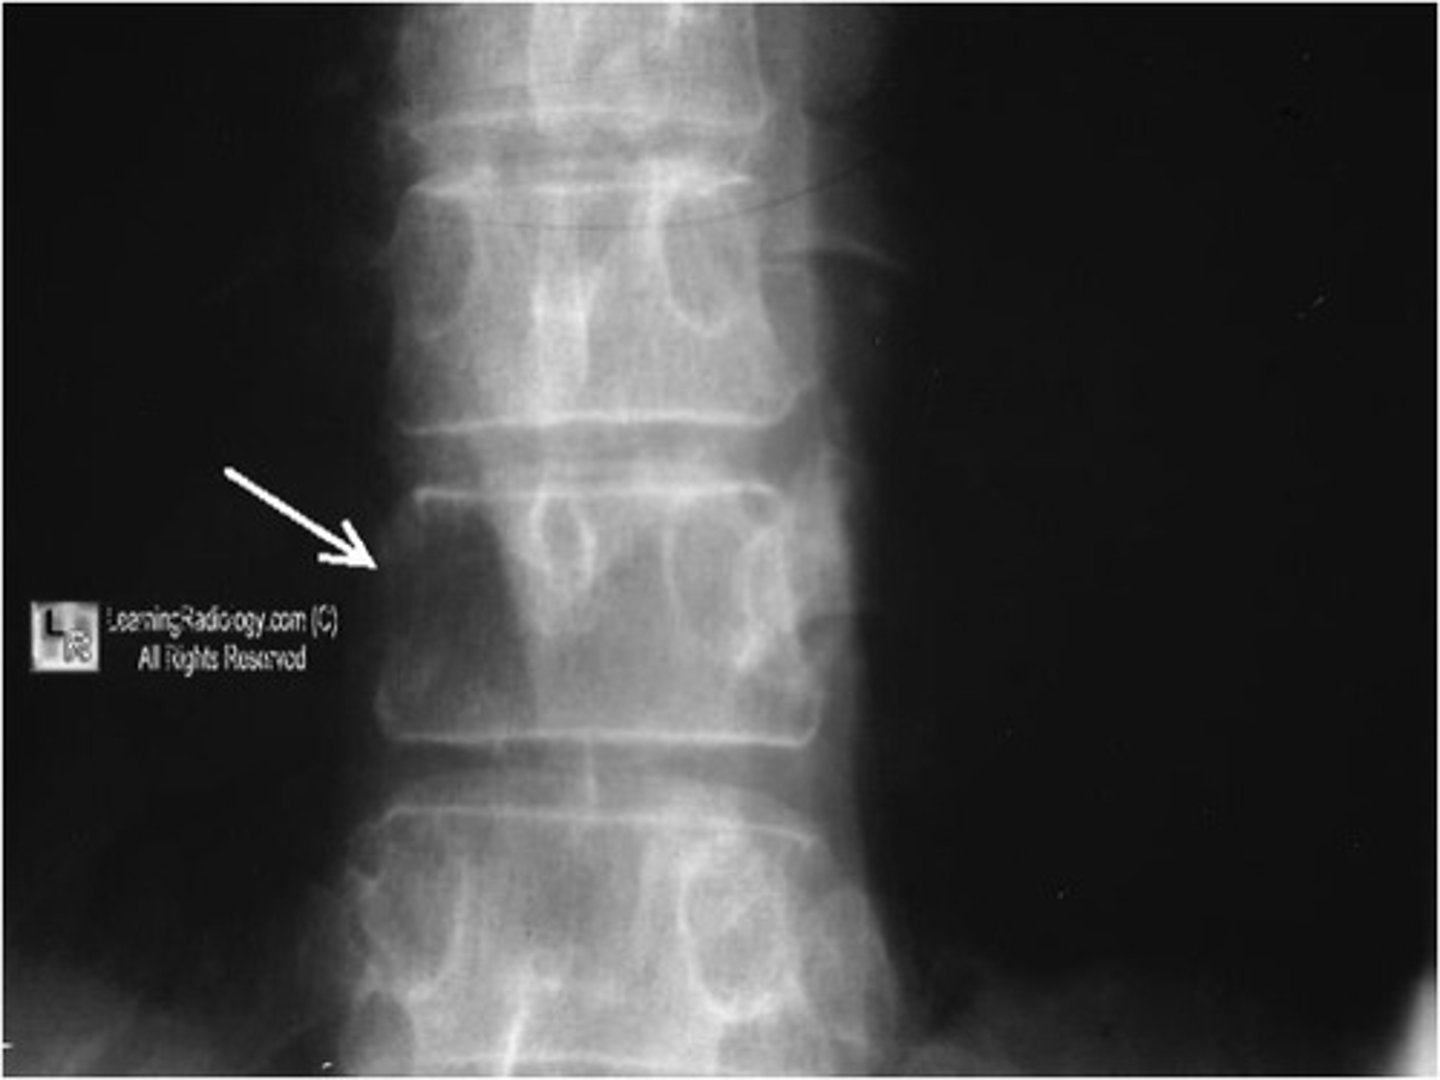

degenerative disk disease

progressive loss of height of the intervertebral disk space

- disk space narrowing

- vertebral body changes

- vacuum disk phenomenon- appearance of air density in disk space